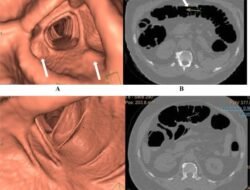

Mengenal, Virtual Colonoscopy Alternatif Cepat dan Nyaman Skrining Kanker Usus

HALOSMI.ID- Guys, Gaya hidup yang modern seperti pola makan kurang sehat dan kebiasaan duduk terlalu…